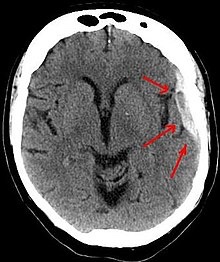

It is important that a person receive medical assessment, including a complete neurological examination, after any head trauma. A CT scan or MRI scan will usually detect significant subdural hematomas.

Subdural hematomas occur most often around the tops and sides of the frontal and parietal lobes.[3][4] They also occur in the posterior cranial fossa, and near the falx cerebri and tentorium cerebelli.[3] Unlike epidural hematomas, which cannot expand past the sutures of the skull, subdural hematomas can expand along the inside of the skull, creating a concave shape that follows the curve of the brain, stopping only at dural reflections like the tentorium cerebelli and falx cerebri.

On a CT scan, subdural hematomas are classically crescent-shaped, with a concave surface away from the skull. However, they can have a convex appearance, especially in the early stages of bleeding. This may cause difficulty in distinguishing between subdural and epidural hemorrhages. A more reliable indicator of subdural hemorrhage is its involvement of a larger portion of the cerebral hemisphere. Subdural blood can also be seen as a layering density along the tentorium cerebelli. This can be a chronic, stable process, since the feeding system is low-pressure. In such cases, subtle signs of bleeding—such as effacement of sulci or medial displacement of the junction between gray matter and white matter—may be apparent.

Fresh subdural bleeding is hyperdense, but becomes more hypodense over time due to dissolution of cellular elements. After 3–14 days, the bleeding becomes isodense with brain tissue and may therefore be missed.[16] Subsequently, it will become more hypodense than brain tissue.